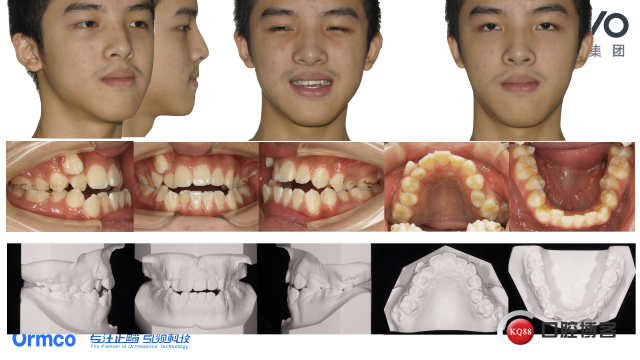

口内检查及模型情况:

中位笑线,系带附着未见明显异常,伸舌居中,舌体运动正常。

恒牙列,牙周良好,磨牙尖牙近中关系,牙弓狭窄,

前牙反合并开合(约2毫米),

上牙弓狭窄伴重度拥挤(10毫米),下牙弓中度拥挤(4毫米),

两侧SPEED曲线深约0.5毫米,

前牙BOLTON比76.5%,全牙BOLTON比88.4%,

上中线右侧偏移4毫米,13颊侧异位,

12 15 25反合,25扭转,

17及27部分萌出未建合,

35舌倾。